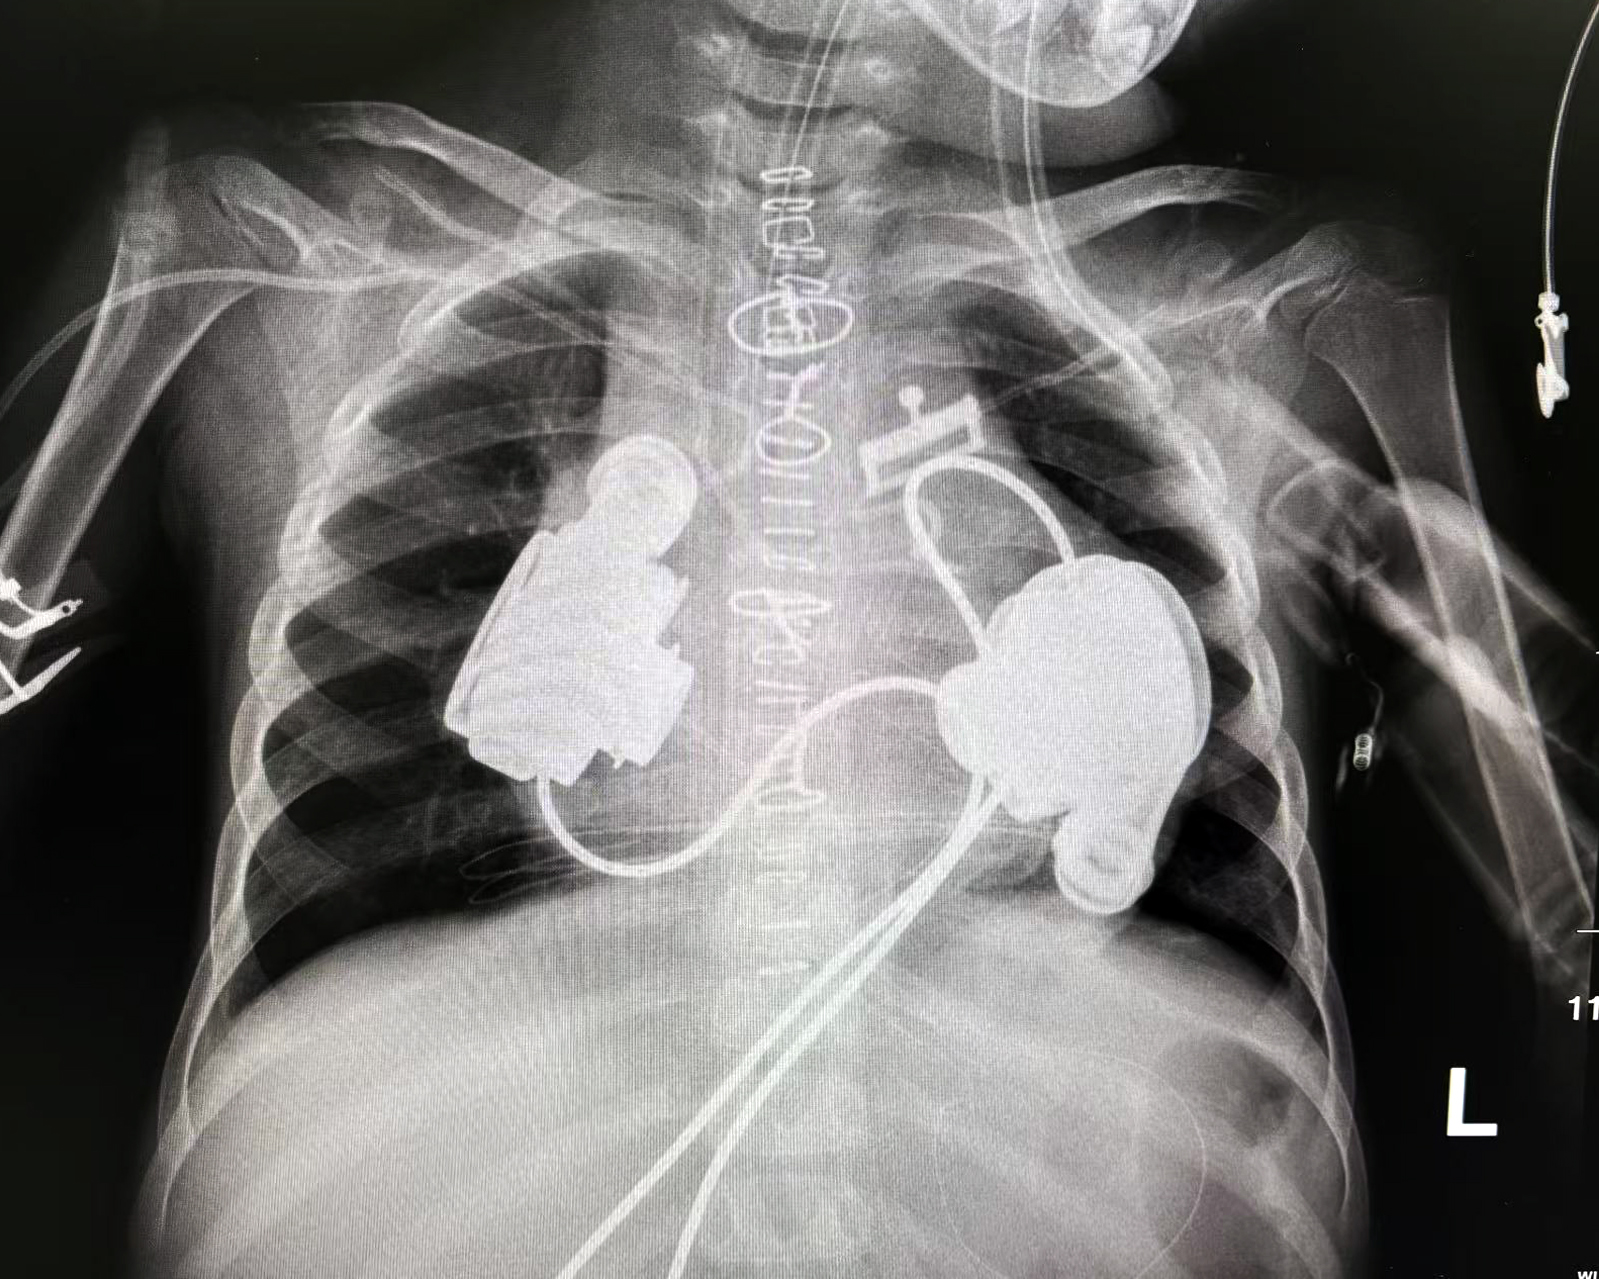

值得注意的是,此次手术还填补了一项全球空白——右心泵设计。此前全球长期没有专用右心泵产品,所有人工心脏主要服务左心。双心衰患者的选择极为有限,基本只能等待心脏移植。而小妮的成功治疗首次在儿童患者身上实现了真正意义的“双心系统”,左右人工心脏同时植入并持续运行40余天,为等待供体赢得了宝贵时间。

双人工心脏植入手术后胸片